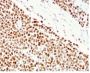

HCT116 or HeLa cell lysate (WB). Human colon carcinoma (IHC).

Antibody target cellular localization

Nucleus

Flow, intracellular (verified), IF (verified), IHC, FFPE (verified), WB (verified)